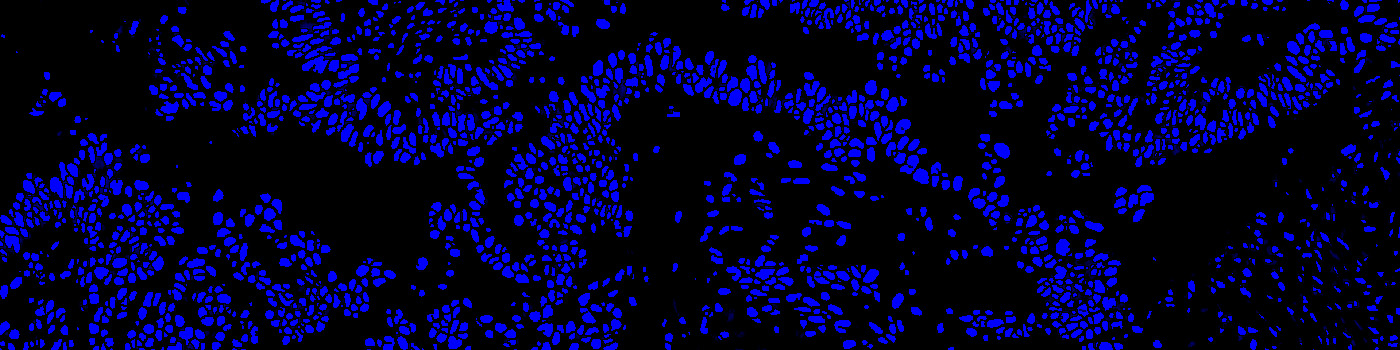

Tissue stained with DAPI

Identification and segmentation of individual nuclei is of interest in many applications. Nuclei can be difficult to detect accurately and precisely across different images using traditional image analysis with feature engineering. This APP utilizes artificial intelligence (AI) for automatic nuclear segmentation in fluorescence images stained with a family of blue dyes for DNA identification. It consists of a pre-trained deep neural network and the APP is ready for use without additional training.

Step 2: Load and run the APP “10169 – Nuclei Detection, AI (Fluorescence)”

The APP was trained using 41,000 annotated nuclei from DAPI stained tissue. The architectural structure of the network is a U-Net which is popular for medical image segmentation. The neural network uses a cascade of layers of nonlinear processing units for feature extraction and transformation, with each successive layer using the output from the previous layers as input. U-Net uses an encoder-decoder structure with a contracting path and an expansive path. For more information of the network architecture, see [1].

Tissue must be labeled with a blue fluorescent dye for DNA staining such as DAPI, Hoechst or Iridium such that all nuclei are labeled.